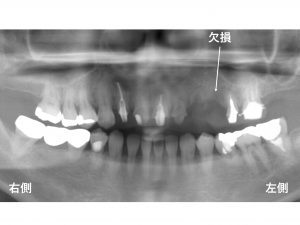

以下が治療前です。

上顎左側に欠損があります。

以下の歯は、根っこだけ残っており、

治療ができる状態ではありません。

抜歯が必要です。

この根っこだけの歯の奥は、欠損しています。

この方は、

現時点で、ブリッジの仮歯が装着されています。